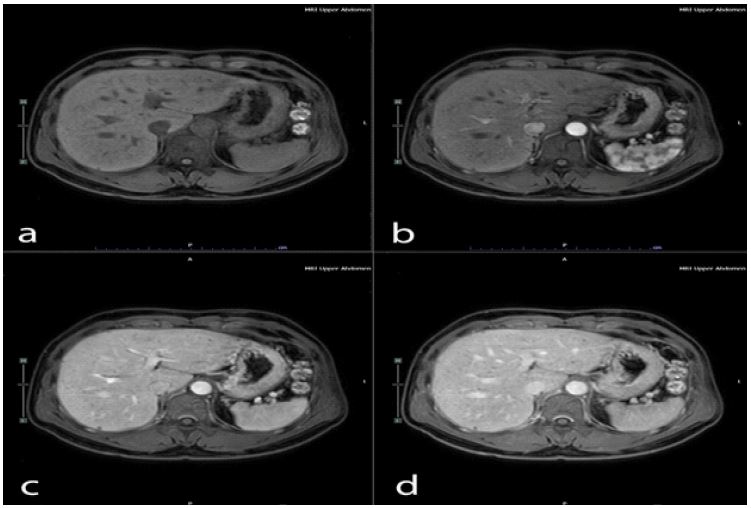

This patient was treated by medication; bronchodilator inhalator for symptomatic relief, molnupiravia (200 mg) 1 tab every 12 hours for 5 days. He was still complaining of fatigue and dyspnea. After failure of medication treatment, the electrocardiography and echocardiography were requested for re-evaluation. The result of that investigation showed normal. The CT chest was performed and reported innumerable Too Small to Characterize (TSTC) lesion scattering both hepatic lobes (Figure 1). The further Magnetic Resonance Imaging (MRI) revealed innumerable cystic lesion in both lobes of liver, (Figure 2). TW showed a signal lower than the liver parenchyma and T2W showed cystic hyperintensity like a ‘starry sky’ (Figure 3).

Figure 1: The CT was reported innumerable Too Small to Characterize (TSTC) lesion scattering both hepatic lobes.

VMCs usually do not cause symptoms and incidental finding with recent noninvasive imaging modalities. Most of biliary hamartoma are composed of small, 5-30 mm disorganized clusters of dilated cystic bile ducts that appear throughout the liver and generally do not communicate with biliary tree [8]. The CT scan of VMCs consists of multiple small, low attenuated areas that do not enhance on contrast injection. MRI of liver and MRCP show low signal intensity on T1-weighed and high signal intensity on T2-weighed images sequences give the liver a ‘starry sky’ appearance [9-11].